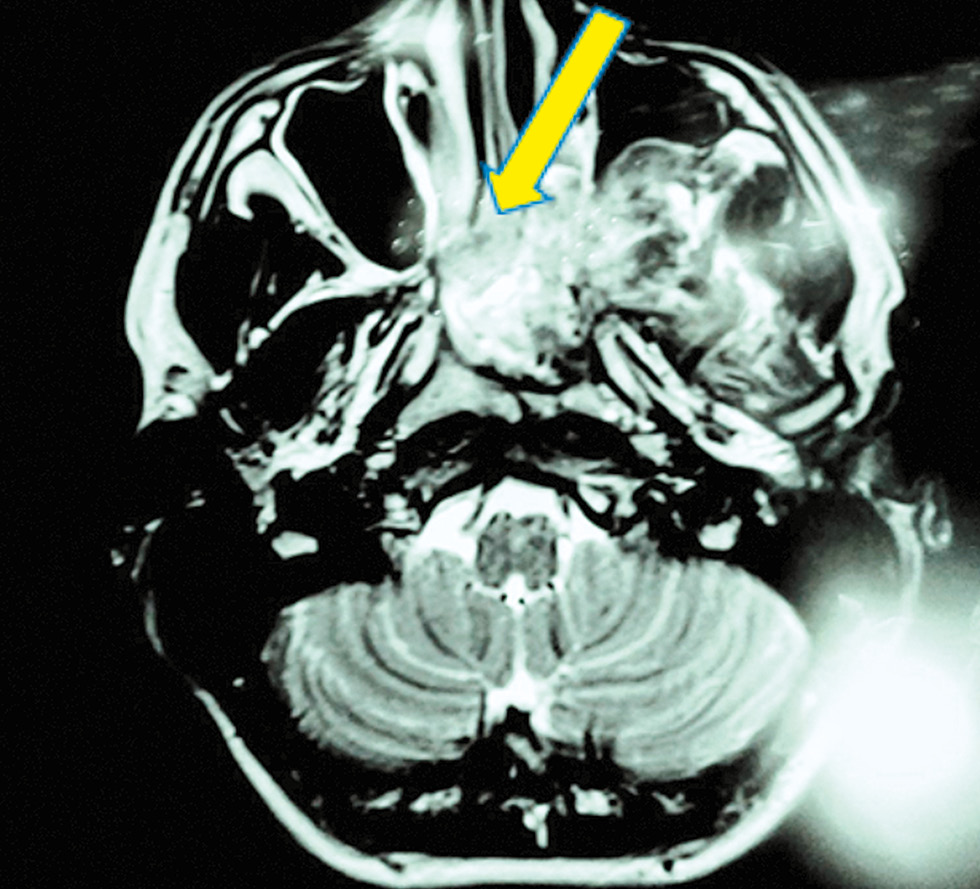

Пациент В., 15 лет, 65 кг, был оперирован по поводу ювенильной ангиофибромы носоглотки, крылонёбной ямки и подвисочной ямки слева. При осмотре обращало на себя внимание полное отсутствие носового дыхания слева. При передней риноскопии выявлялась опухолевая ткань, которая обтурировала левый носовой ход в средних его отделах. Лимфатические узлы шеи не увеличены. По данным компьютерной томографии лицевого скелета с внутривенным контрастированием, получена РКТ-картина, соответствующая фиброзной дисплазии клиновидной кости. Проведённое КТ-исследование головного мозга с внутривенным контрастированием показало отсутствие патологических изменений в головном мозге. По данным МРТ в области подвисочной ямки слева имеется опухолевидное образование, распространяющееся на задние отделы носовых ходов, носоглотку, левую верхнечелюстную пазуху, задние отделы ячеек решетчатого лабиринта (рис. 6).

Рис. 6. МРТ-картина области подвисочной ямки слева (ангиофиброма носоглотки, крылонёбной ямки и подвисочной ямки слева) / Fig. 6. MRI picture of the region of the sub-temporal fossa on the left (angiofibroma of the nasopharynx, pterygoid fossa and the sub-temporal fossa on the left)